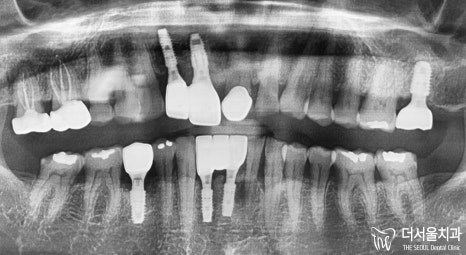

문정동치과 이가 흔들려요 앞니 어금니 임플란트 뼈이식 받아 해결한 증례

검사 결과,

생각했던 것보다 많이 흔들려서

이를 발치 후 임플란트 수술을

받으셔야 되는 상황이었습니다.

내원 당시 구강 속을 살펴보면

잇몸이 붓고 내려가 있으며

떨어져버린 어금니가 있고,

여기저기 많이 닳아있으며

아예 상아질이 드러난 것을

문정동치과 에서 체크할 수 있었는데요.

치조골 두께를 확인해서

얼마나 더 깊고

튼튼하게 고정시켜줄 수 있을지

길이까지 파악하여

적합한 픽스처를 선택 후,

뼈이식을 해야 된다든지

신경관과 가깝지는 않은지

조심해야될 사항은 크게 없었기에

어렵지 않게 잘 심어드릴 수 있었습니다.

그런데 앞니는 조금 상황이 달랐습니다.

육안으로 봤을때도

붓고 염증이 있었기에

뼈 두께나 깊이를 확인하여

미끄러지지 않는게 중요했으며,

GBR(골유도재생술)을 이용하여

모자란 뼈를 재생시켜

임플란트 식립이 더욱 잘 되게끔

기반을 튼튼히 다져드려야 되었습니다.

#27은 상악동과의 거리가

가까웠기 때문에

거상술을 통하여

뼈이식을 해드려 기반을 만들어야 되었습니다.